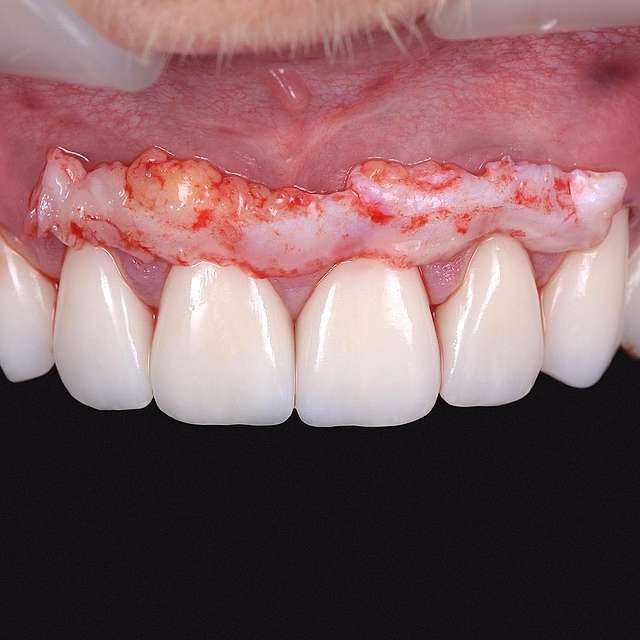

A gingival graft is a micro-surgery that will transplant a bulk of soft tissue - free gingiva or connective tissue ( the internal layer of gingiva ) to cover a soft tissue defect. Usually this type of procedures is required to augment implants, or to cover defects caused by periodontal disease or trauma. The grafts are harvested from the third molar region or the palate, and are transported where they are needed.

This type of procedure is a very delicate one, using the same type of blades like the ones used in ophthalmology and the sutures are also very thin. The sutures will be removed after 7-14 days, depending on the case, when primary healing is achieved. The maturation of the graft will take roughly 90 days, this is the reason why, when placing implants we prefer to also do the graft, so we can sync the healing time for both procedures.

Using tissue grafts to correct tissue defects

Using tissue grafts to correct gingival levels or cover recessions